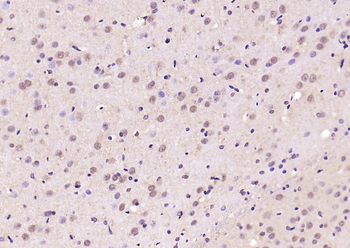

50 μl, 100 μlPhospho-Smad3 (Thr179) Rabbit Polyclonal Antibody [orb313112]

FC, ICC, IF, IHC-Fr, IHC-P

Bovine, Canine, Equine, Porcine, Sheep

Human, Mouse, Rat

Rabbit

Polyclonal

Unconjugated

100 μl, 200 μl, 50 μlSMAD7 Rabbit Polyclonal Antibody [orb500819]